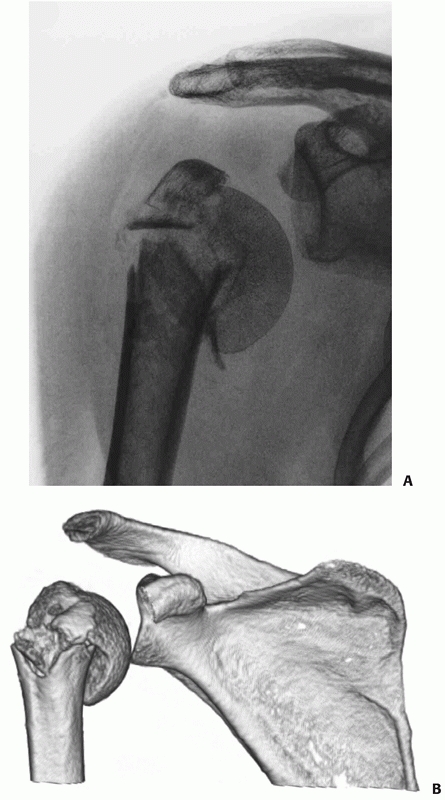

![]() |

FIGURE 35-17 A. “Double-shadow” on the anteroposterior radiograph (arrow) is pathognomic of a head-split fracture. The split is also seen on the modified axial view (B) but the extent of head involvement is best assessed using a computed tomography scan (C). The white arrows show the head-split.

FIGURE 35-18

In Type I anterior fracture-dislocations, the humeral head is engaged on the anterior glenoid rim, as shown on the anteroposterior radiograph (A), the schematic diagram (B), and anteroposterior and superior three-dimensional computed tomography reconstructions (C,D). Internal fixation of these fractures is associated with a low risk of osteonecrosis (E,F). (continues) |

FIGURE 35-18 (continued)

In Type II anterior fracture-dislocations, the humeral head is not engaged on the anterior glenoid rim, as shown on the anteroposterior radiograph (G), the schematic diagram (H), and anteroposterior and superior three-dimensional computed tomography reconstructions (I,J). The humeral head dislocates through a rent in the inferior capsule (K). (continues) |

It is usually devoid of soft tissue attachments and at higher risk of osteonecrosis. Iatrogenic displacement of the initially impacted shaft from the head may occur during attempted relocation of the shoulder, as seen on these premanipulation and postmanipulation radiographs that were taken in the emergency department (L,M). |